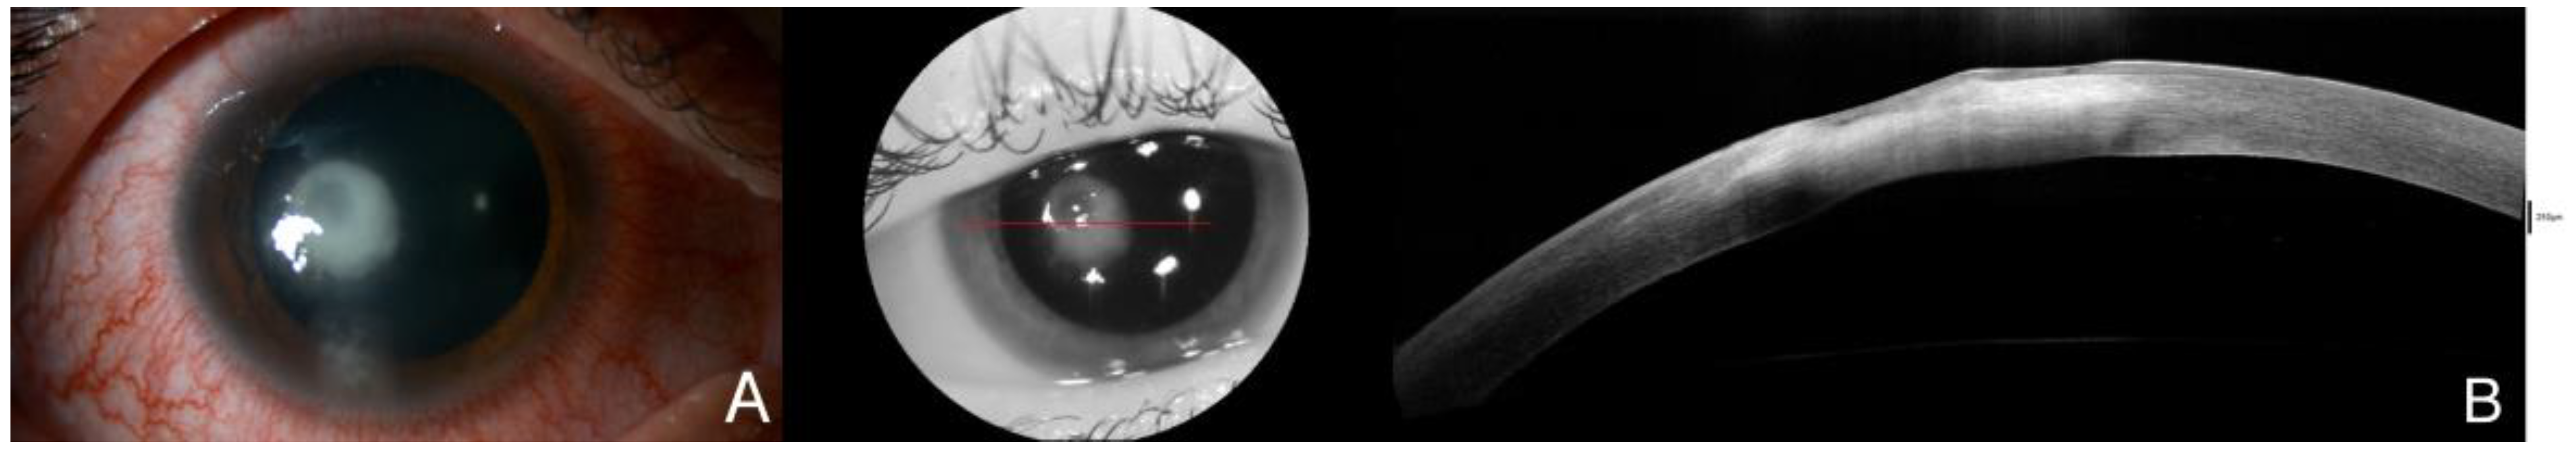

Figure 2.

(A). Clinical evolution with endothelial infiltrates and expansion of the infiltrate, as well as corneal necrosis hyperreflective in AS-OCT, with small cystic spaces next to the epithelium. The initial culture from the corneal sample returned positive for Streptococcus oralis resistant to eritromicine, clindamicine and tetracycline. Due to these results and a torpid clinical course without symptomatic improvement, appearance of endothelial deposits and impairment of stromal edema in AS-OCT with hyperreflectivity reaching deeper layers (B) and BCVA loss to 0.3, the treatment was updated with interruption of the fortified topical antibiotics, which were switched to moxifloxacin and linezolid. Natamicyn was added to the treatment in substitution of voriconazole. Two days later, the endothelial deposits disappeared and the patient related symptomatic improvement, but a week after, the BCVA in the right eye was severely reduced to 0.05. The red line is correspondene of the en face picture with the selected section on the AS-OCT.